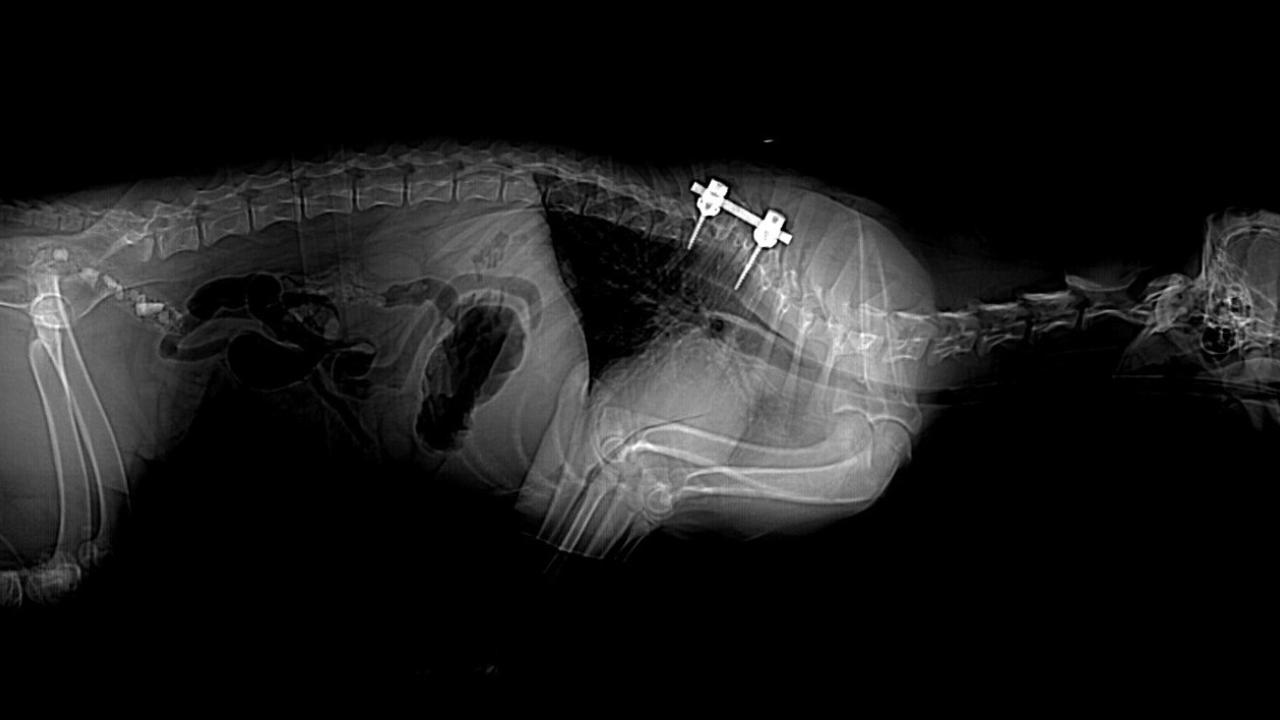

To further evaluate her condition, the team coordinated with Anesthesia and Diagnostic Imaging Services to perform a CT scan. The scan revealed multiple vertebral anomalies from her 4th thoracic vertebrae (T4) to her 9th thoracic vertebrae (T9) (most severe from T5 to T8) resulting in marked spinal curvature and spinal cord compression at T6 to T7, and in narrowing of the spinal canal. All this led the neurologists to believe that her condition was more likely congenital rather than traumatic.

Dr. Lim proceeded with Kailana’s surgery when she reached 6 months of age. The delicate 7-hour operation involved a partial removal of the T6 to T7 vertebrae (a procedure called corpectomy) at the site of the most severe spinal cord compression, followed by stabilization of the spine using pedicle screws and rod.